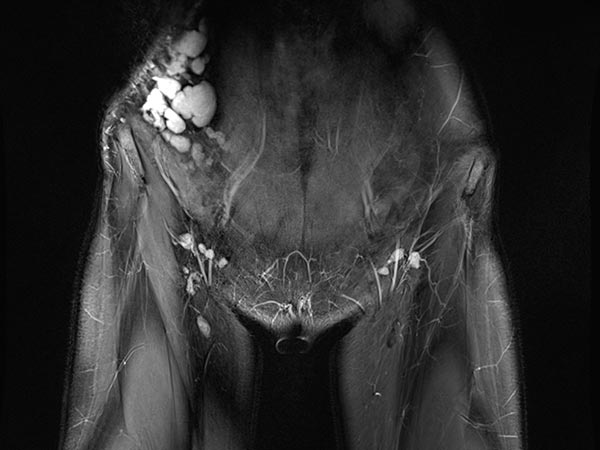

Koronare, T2-gewichtete, fettunterdrückte MRT des Unterbauchs auf Höhe der Leisten. Unauffällige Leistenlymphknoten. Die lymphatische Malformation der Bauchwand stellt sich in großen, dysplastischen, ballonartigen, gekammerten Zysten dar, die stark hyperintens (weiß) sind.

Gleiche Schnittführung in der nativen T1-Wichtung (MRT). Die Zysten der lymphatischen Malformation sind isointens zur Muskulatur. Damit keine lokale Einblutung.

Die transversale, T2-gewichtete, fettunterdrückte MRT auf Höhe der Beckenschaufel zeigt die Ausdehnung der LM auch im Bereich der rechten Flanke. Nur die epifaszialen Anteile der Bauch- und Rumpfwand sind betroffen.

Die transversale, T1-gewichtete, fettunterdrückte MRT nach Kontrastmittelgabe zeigt nur ein minimales Enhancement der dünnen Wände der lymphatischen Malformation. Dies ist typisch für eine LM.